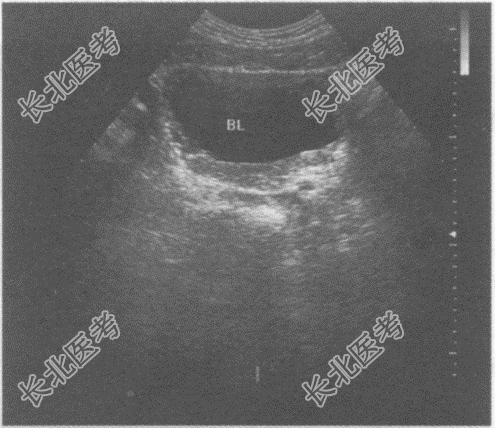

- 单项选择题临床资料:男, 60岁,自述排尿分叉、不畅, 患慢性前列腺增生十余年。

超声综合描述:横切4: 00~8:00处可见扁平形中等回声区, 表面粗糙,内回声不均, 最大厚度1.1cm,后方无声影, 体位变动形态无改变。

超声提示: A、膀胱实性占位

B、膀胱沉积物

C、腺性膀胱炎(轻度弥漫增厚型)

D、膀胱结石

E、膀胱肿瘤